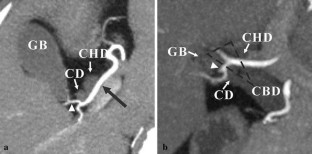

Assessment and classification of cystic arteries with 64-detector row computed tomography before laparoscopic cholecystectomy

Major complications of laparoscopic cholecystectomy are bleeding and bile duct injury, and it is necessary to clearly identify structures endoscopically to keep bleeding and injury from occurring. The aim of this study was to depict the anatomical variation between cystic arteries among patients using 64-detector row spiral computed tomography (CT) prior to laparoscopic cholecystectomy.

A total of 78 patients (31 men, 47 women) who underwent cholecystectomy were examined preoperatively using 64-detector row spiral CT between April 2012 and June 2013. The origin and number of cystic arteries and their relationship with the Calot triangle was evaluated by two independent observers. CT images were compared with laparoscopic cholecystectomy results.

The cystic arteries were delineated by CT in 73 of the 78 patients. The relationship between the cystic arteries and the Calot triangle was identified in 71 of the 78 patients. One cystic artery was found in 53 (73 %) of the 73 patients, while two cystic arteries were found in 20 (27 %) of the patients. A total of 55 (60 %) of the 91 cystic arteries passed through the Calot triangle. The remaining 36 cystic arteries (40 %) passed anterior, posterior, or inferior to the cystic duct. The relationship between the cystic arteries and the Calot triangle detected by CT was in agreement with the surgical records for all patients.

The configuration of the cystic arteries and their relationship with the Calot triangle can be identified using 64-detector row CT before laparoscopic cholecystectomy.

Fig. 1